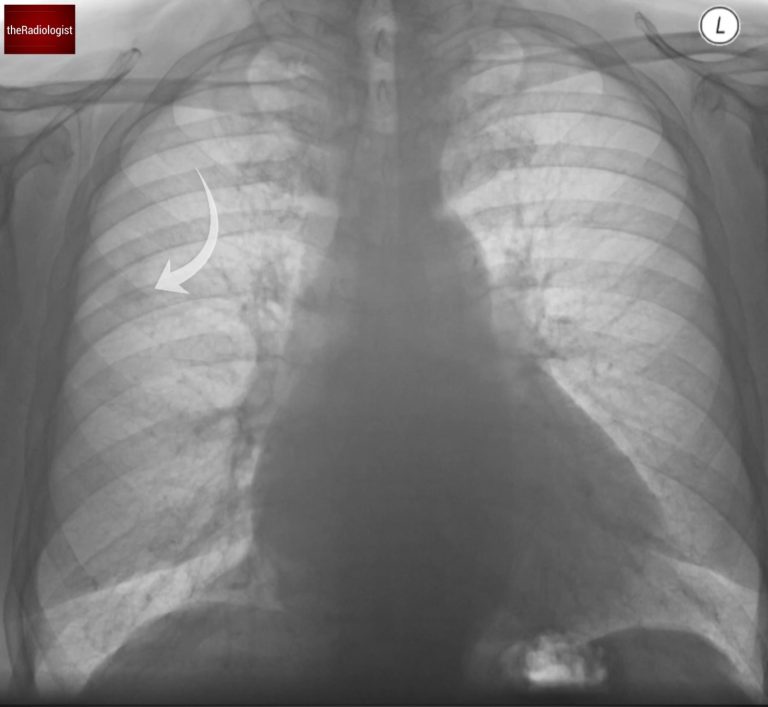

Now review the lungs – there are different ways to do this but I like to take ‘upper’, ‘mid’ and ‘lower’ zones in turn comparing side by side. You are looking for nodules or masses, consolidation or any opacification you may not have seen so far.

One way to review the lung is to split the lung into ‘zones’ and compare side by side. If we do so in this case we will see a small nodule within the right mid zone.